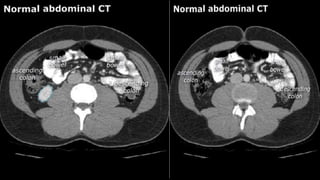

• A few characteristics of normal anatomy:

• Portal venous phase: the parenchyma of the

liver/spleen/pancreas is homogeneously enhanced.

• Intra-abdominal fat has the density of fat (HU -50 to -100;

see the X-ray/CT technique course for more information

about Hounsfield units); similar to normal subcutaneous fat.

If not, there may be ascites or fatty infiltration.

• A fewcharacteristics of normal anatomy: • Portal venous phase: the parenchyma of the liver/spleen/pancreas is homogeneously enhanced. • Intra-abdominal fat has the density of fat (HU -50 to -100; see the X-ray/CT technique course for more information about Hounsfield units); similar to normal subcutaneous fat. If not, there may be ascites or fatty infiltration.